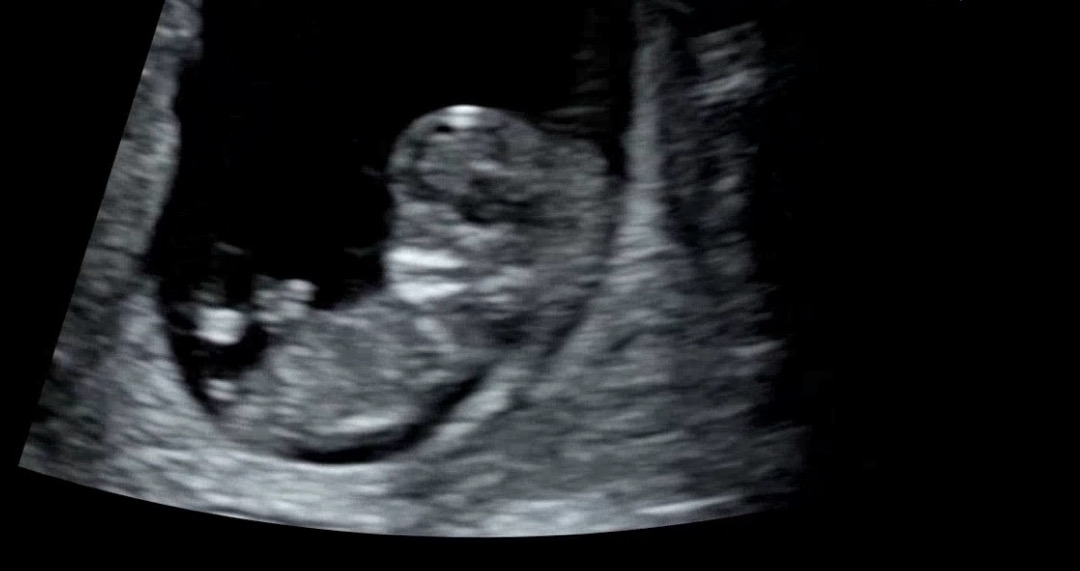

11주 각도법으로 성별 알수있나요??

설 지나서 병원 일정 있는데 넘 궁금하네요~~ 배초음파라서 화질이 넘 안 좋긴한데ㅠ 각도법으로 성별 알수있을까요??

아니요 11주땐몰라요 12주때도 척추와 다리위치로 예싱해보는거구요